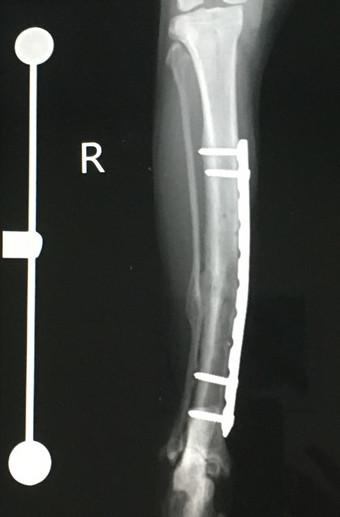

2021年6月、骨折してから約10ヶ月&プレート抜去手術(1回目)から3ヶ月経過しての検診に行ってきました。

レントゲン撮って「順調です」って言われてお会計してくるルーチン。

もう飼い主も先生も今さら特にコメントもなくw。

予定通り次回残りのプレート抜去のスケジュールを決めてきました。

7月中旬ー。